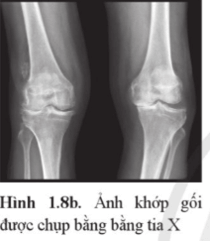

Luyện tập 3 trang 30 Chuyên đề Vật Lí 12: Giải thích vì sao có vùng màu sẫm, vùng màu sáng ở ảnh chụp khớp gối bằng tia X trong Hình 1.8b.

Giải thích vì sao có vùng màu sẫm, vùng màu sáng ở ảnh chụp khớp gối bằng tia X

Lời giải:

Khi xuyên qua các mô mềm, chùm tia X ít bị giảm cường độ nên trên phim sau khi tráng, vùng tương ứng với các mô mềm có màu sẫm. Vì xương làm giảm cường độ chùm tia X nhiều hơn so với các mô mềm nên trên phim sau khi tráng vùng tương ứng với vị trí của xương có màu sáng hơn.